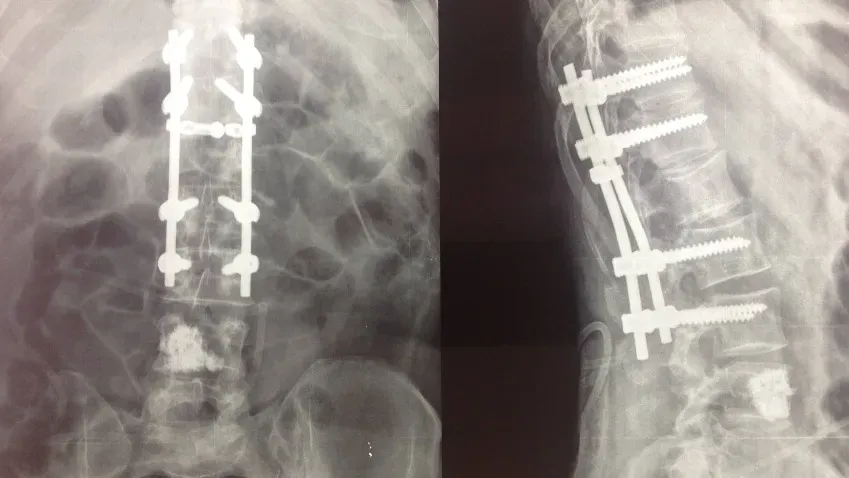

Neurosurgery: искусственный интеллект поможет идентифицировать спинномозговые имплантаты